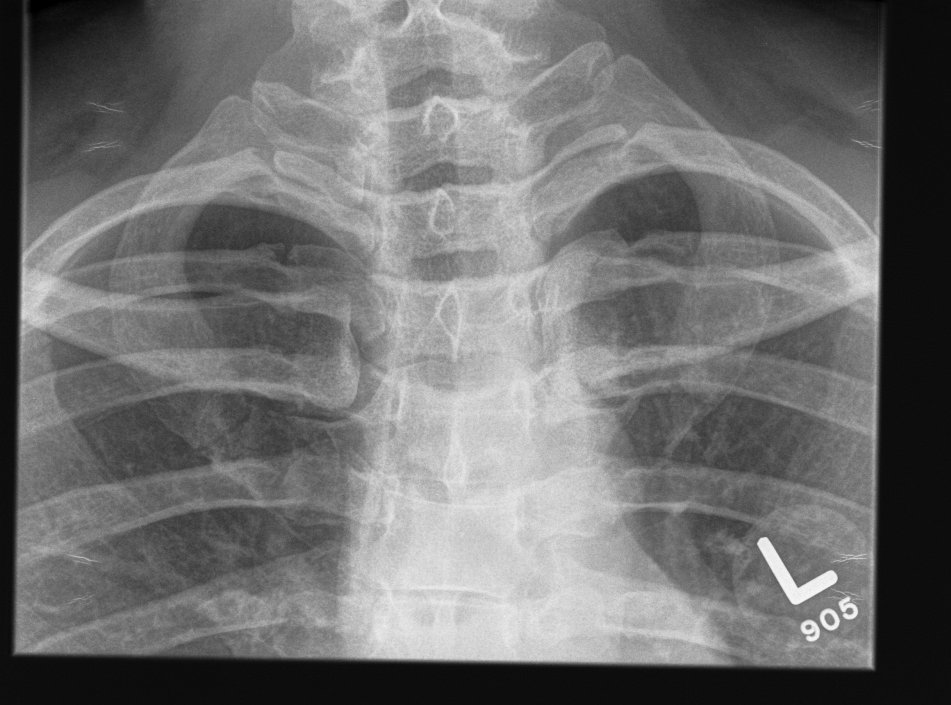

Congenital Vertical Talus

Definition

Rockerbottom foot / Persian Slipper Foot

Epidemiology

Uncommon

50% bilateral

Doesn't delay walking

- may present in toddler with callus under talus head

Associations

Congenital anomalies

- CNS disorders

- spina bifida & diastematomyelia ~10%

- arthrogryposis

- neurofibromatosis